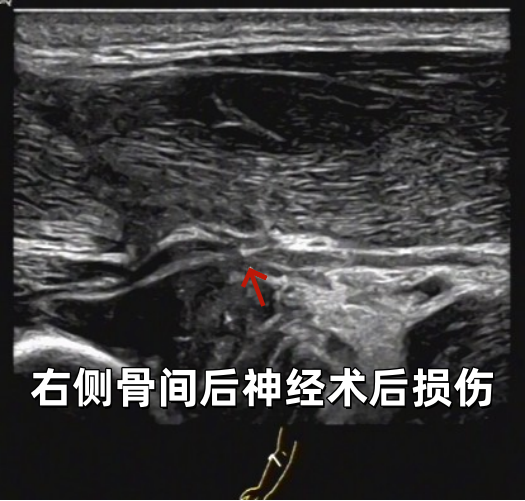

超声影像

当超声探头滑过小轩疼痛无力的四肢时,屏幕上的图像揭示了关键线索:其双臂及大腿的肌肉呈现出特征性的纹理紊乱、结构模糊。

这一清晰直观的影像证据,为临床诊断提供了坚实依据,高度提示为皮肌炎。

部分病例展示